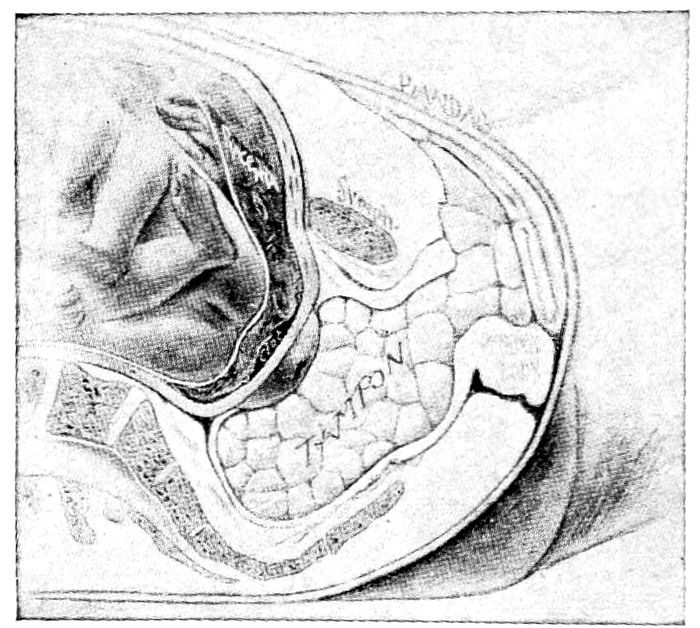

| 88. |

204 |